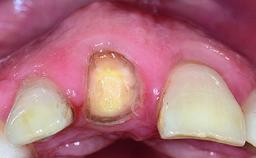

Replacement of a Compromised Upper Right Central Incisor: Hard- and Soft-tissue Augmentation, Late Placement of an RC Bone Level Implant

A 36-year-old male patient with a compromised maxillary central incisor was referred by his general dentist for consultation. The patient’s chief complaints were the gradual debonding of a temporary crown on the right central incisor and unsatisfactory esthetics due to an increasing diastema between the right central and lateral incisors. The patient reported a traumatic event some years previously, when a crown had been placed after root-canal treatment. The referring dentist wanted to provide a new crown restoration, but was concerned about the condition of the residual root. Anamnesis was negative for any other dental or periodontal pathology in the remaining dentition. The patient reported taking no medications: He was a smoker (10 to 15 cigs/day) and had realistic esthetic expectations.

Soft Tissue Anatomy Intact Defective

Soft Tissue Contour and Volume Slightly compromised